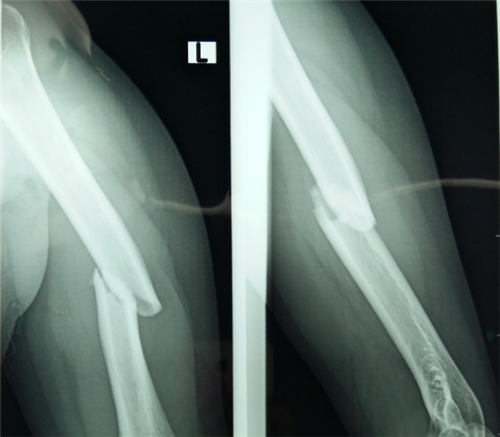

生活中,磕磕碰碰在所难免。四肢骨折也成为了较常见的骨科疾病之一。为了更好的诊断和治疗,我们需要把握四肢骨折的症状体征。…「查看详情」

四肢血管损伤无论在平时还是战时都比较常见,常与四肢骨折和神经损伤同时发生,多为动、静脉同时损伤,四肢血管血管损伤常易致命的大出血和肢体缺血坏疽或功能障碍。…「查看详情」